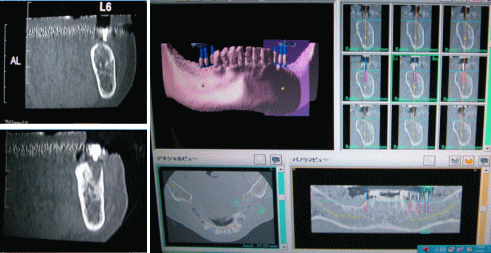

CT撮影

特に、インプラント等の高度な歯科診療では、術前の診断が大変重要となります。

従来のレントゲン撮影では、充分な診断が、出来ない場合も少なくありません。

当院では、撮影したCT画像を、特殊なソフトによって解析・再構成し、安全なインプラント治療の為に、コンピュータによるインプラント埋入のシミュレーションも行っております。